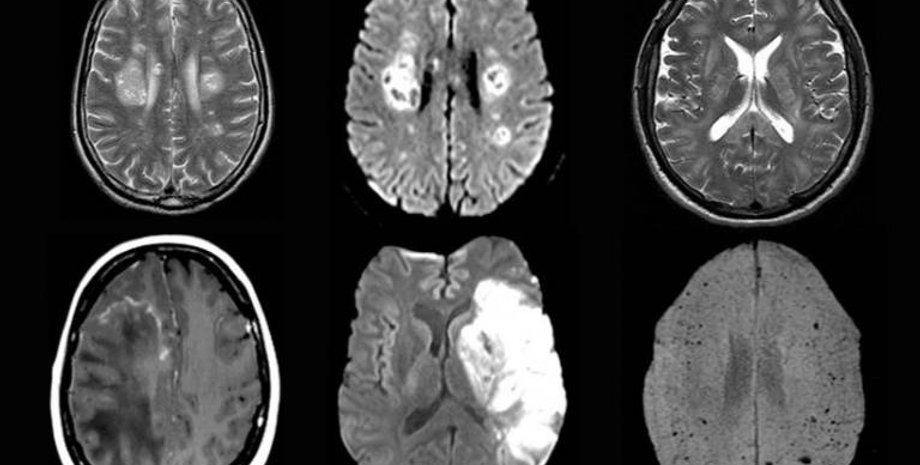

Фото: UCL

Коронавирус может привести к воспалению головного мозга, инсульту и повреждению нервов.

Они изучили протекание болезни у 43 человек в возрасте от 16 до 85 лет. У 10 из них была выявлена временная дисфункция мозга, а у 12 — его воспаления, некоторые из которых являлись острым диссеминированным энцефаломиелитом. Также наблюдались другие серьезные повреждения, например инсульты.

При этом у некоторых пациентов в исследовании не было серьезных респираторных симптомов, и неврологическое расстройство было основным проявлением COVID-19.

При этом вирус SARS-CoV-2, вызывающий COVID-19, не был обнаружен в мозговой жидкости ни у одного из протестированных пациентов. Это позволяет предположить, что вирус непосредственно не воздействовал на мозг, вызывая неврологическое заболевание. Необходимы дальнейшие исследования, чтобы определить, почему же у пациентов развивались эти осложнения.

У некоторых пациентов исследователи обнаружили указания на то, что воспаление мозга, вероятно, было вызвано иммунным ответом организма на заболевание.